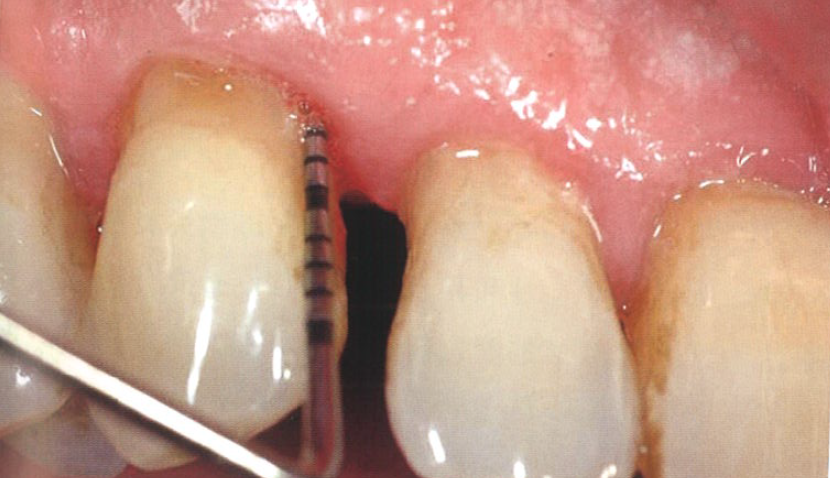

在为期15年的牙周维护治疗期间,由于患者的疏忽偶尔没有按时复诊,就诊时观察到牙周炎症的复发。图1显示探诊深度为7 mm,并伴有探诊出血。

图1  患者的牙周探诊深度为7 mm,且伴有探诊出血